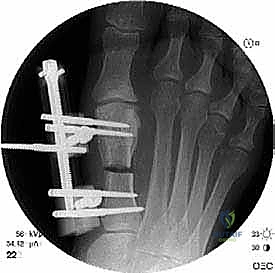

الخطوة الرابعة: الإطالة والطعوم العظمية (Bone Grafting)

يتم إبعاد طرفي العظم المقصوص بلطف للوصول إلى الطول التشريحي المطلوب (والذي تم حسابه مسبقاً في صور الأشعة). لملء الفراغ الناتج عن الإطالة، يتم استخدام طعم عظمي (Bone Graft).

* الطعم الذاتي (Autograft): غالباً ما يتم أخذ قطعة صغيرة من العظم من كعب المريض (عظم العقب) أو من عظم الحوض، وهو الخيار الأفضل لأنه يحفز الالتئام السريع.

* الطعم الصناعي أو العظم البنكي (Allograft): يمكن استخدامه في بعض الحالات لتجنب إحداث جرح إضافي.

الخطوة الخامسة: التثبيت الداخلي القوي (Internal Fixation)

لضمان التئام العظم في وضعه الجديد والطويل، يجب تثبيته بقوة شديدة. يستخدم الدكتور هطيف أحدث الشرائح المعدنية التيتانيوم ذات الزاوية الثابتة (Locking Plates) والمسامير الدقيقة. هذا التثبيت القوي يمنع أي حركة بين العظام ويسمح ببدء العلاج الطبيعي في وقت مبكر.